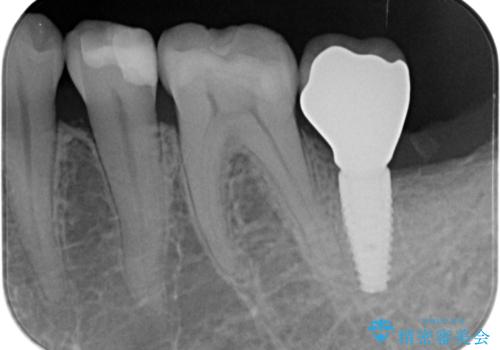

歯の抜去を行い、骨の造成を含めたインプラントによる咬合機能の回復を図ります。

- 44万円(インプラント・チタンカスタムアバットメント・ジルコニアクラウン・仮歯)費用は治療当時の料金となります